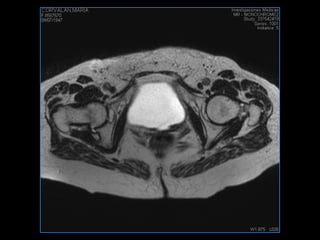

PROTOCOLO pelvis SAG T2, Y FAT SAT (FINOS) AXIAL T1  AX FAT SAT CON   GADOLINIO :  AX T1 Y COR T1 SAT: NO  FASE: RL THK: 3MM  COIL:  GAP: (FACTOR 1.4) 1MM FOV: 40 CM NEX:2 SINCRONIZACION RESPIRATORIA EN 3 O 4 CICLOS ALE